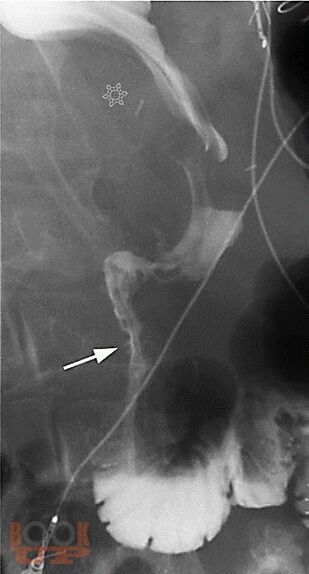

В учебном пособии представлена современная информация об эпидемиологии, классификации, клинике, диагностике, принципах и результатах лечения рака желудка. Особое внимание уделено перспективным методам первичной и вторичной диагностики рака пищевода.